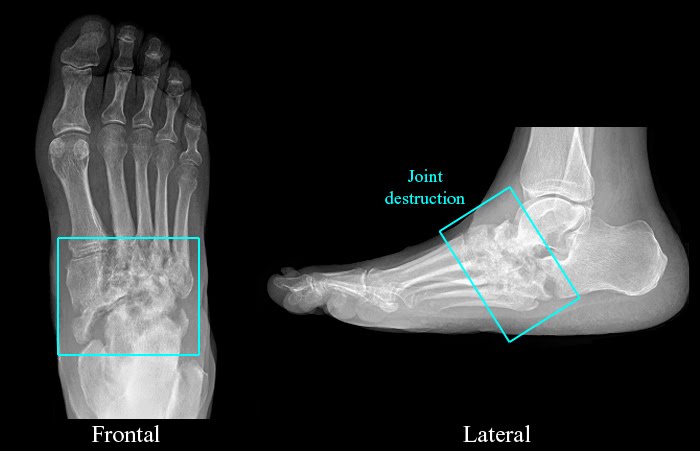

-There is preservation of bone mineral density.-There is osseous fragmentation, midfoot fractures, and destruction of multiple tarsometatarsal joints.

Neuropathic arthritis is caused by chronic repetitive trauma to insensitive joints. Underlying causes include diabetes, steroid use, trauma, alcoholism, multiple sclerosis, spina bifida, and syringomyelia. The radiologic findings are frequently discussed at the “6 D’s:” Density i.e. bone density maintained, Dislocation, Debris, Distention i.e. soft tissue swelling and joint effusions, Destruction, Disorganization.